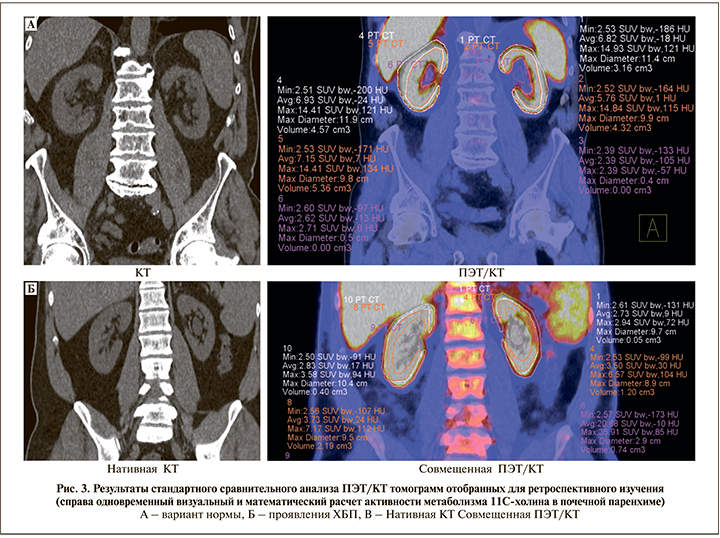

В таблице представлены цифровые данные ПЭТ/КТ-метаболизма 11С-холина, отразившие состояние жизнеспособности паренхимы почек, из которых видно, что снижение тропности паренхимы почек к 11С-холину до 20% относительно показателей структурно и функционально состоятельной паренхимы, не сопровождались визуальными КТ-проявлениям деформации контура почек. В то время как снижение тропности паренхимы более чем на 30% визуально совпадало с появлением рентгенологических признаков, характерных для необратимых изменений в паренхиме почек (искривление контура, деформация чашечно-лоханочной системы, уменьшение размеров) (рис. 3).

По результатам сравнительного визуального и математического анализов представленных томограмм можно заключить, что у пациента Б., как и у пациента А., не имевших на момент обследования анамнестических и клинико-лабораторных проявлений ХБП, имело место снижение метаболизма меченых биомолекул в проекции коркового и мозгового слоев обеих почек более чем на 40% относительно условно рассчитанной нормы (SUVmax 11,6±1,0 g/ml), что сопровождалось уменьшением диаметра анализируемой почечной паренхимы на 10%.